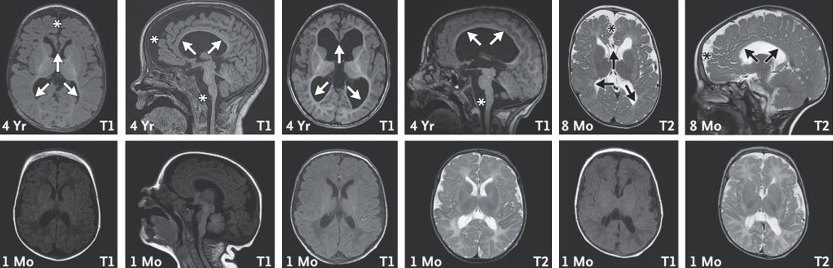

Lab tests showed that the children’s cells had elevated CHD2 levels, just as the Weizmann researchers had seen in the mouse models. MRI scans revealed that in the first years of the children’s lives, there had been progressive damage to white matter in the brain, the tissue responsible for refining and coordinating signals between nerve cells.